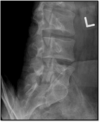

1

Lateral Lumbar Spine Criteria

- open disc spaces and foramina (angle) - Superimposed pedicles (rotation)